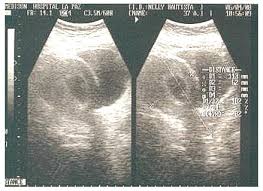

La ecografía abdominal se considera a menudo como la primera opción de imagen en mujeres embarazadas con sospecha de apendicitis, debido a su disponibilidad, seguridad y falta de exposición a la radiación. Sin embargo, es importante tener en cuenta que la visualización del apéndice en la ecografía puede ser difícil, especialmente durante el embarazo, debido a la posición alterada del órgano y a la presencia de gas intestinal que puede interferir con la imagen. Por lo tanto, la no visualización del apéndice en la ecografía no descarta por completo la posibilidad de apendicitis y puede requerir la realización de otras pruebas de imagen.